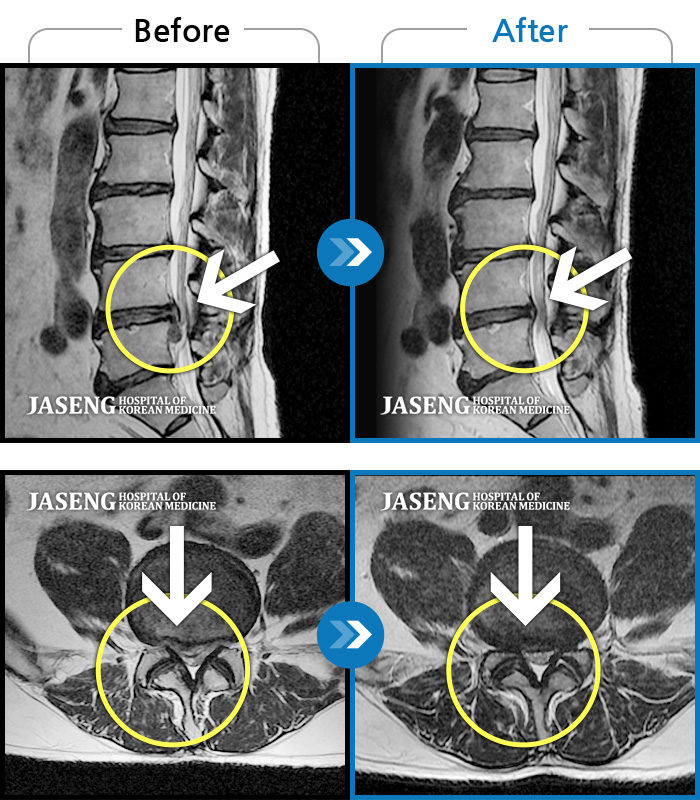

MRI 치료사례

요부 및 우하지 극통으로 거동이 불가